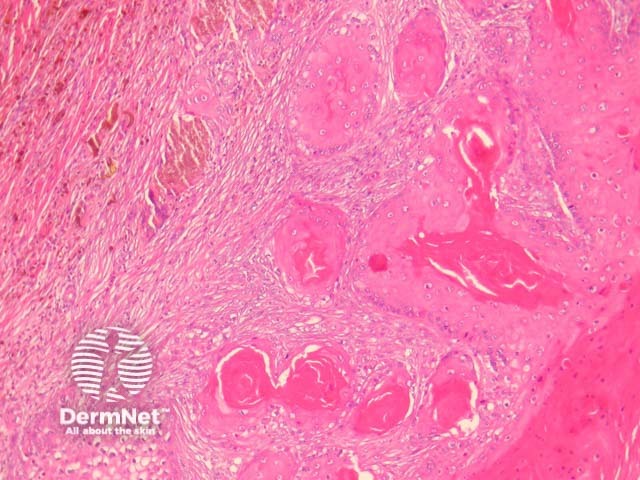

The individual cystic islands resemble regular trichilemmal cysts and often calcify (figure 2). Rupture is common, and this leads to surrounding fibroplasia and foreign body giant cell reaction (figure 3). The lining epithelium is a stratified squamous epithelium exhibiting trichilemmal keratinization (figure 4).

Figure 3